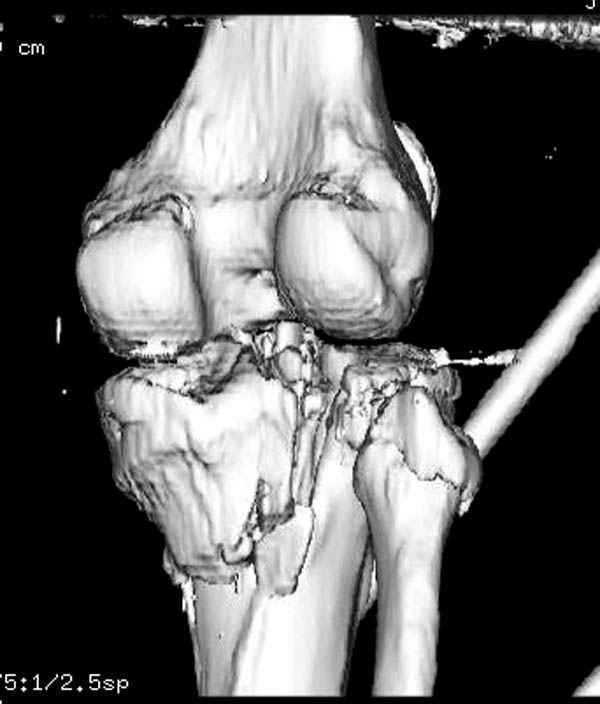

Пациенту сделали КТ - ухитрились сделать на шине Белера (не давал положить прямую ногу) - срезали передний отдел. Планируется на пятницу (24.12) на операцию - синтез длинной мыщелковой LCP-пластиной Synthes :). Отек ближе к слову умеренный (окружность голени +4 см по сравнению со здоровой). КТ и снимок на вытяжении прилагаются.

На представленных предоперационных срезах КТ огромный задне-медиальный фрагмент расположен больше кзади, чем медиально. Для планирования, кроме поперечных срезов, надо ориентироваться на корональные срезы, которые укажут топографию верхушки медиального фрагмента.